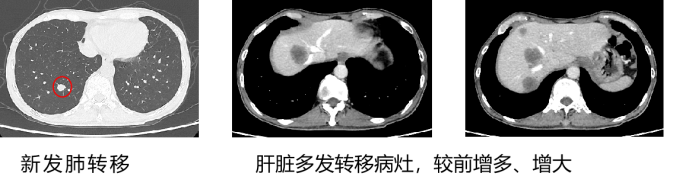

• 2周期联合治疗后疗效评估:PR

• 影像学:增强CT(2025年1月3日):双肺多发微小实性结节,部分较前消散;肝脏多发转移灶较前缩小、减少,病灶仍有活性。

• 6周期联合治疗后疗效评估:SDa.

• 影像学:增强CT2025年3月13日):双肺多发微小实性结节,大致同前;肝脏多发转移灶较前稍缩小,病灶仍有活性。

• 3周期维持治疗后疗效评估:SD.

• 影像学:增强CT(2025年5月20日):双肺多发微小实性结节,大致同前;肝左内叶病灶范围较前稍小,活性范围较前缩小,左外叶病灶范围较前稍大,其余病灶大致同前,部分病灶仍有活性。

image.png